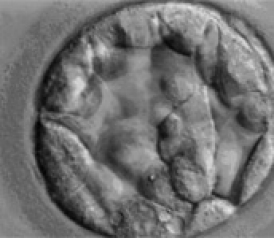

If you go in for fertility treatment, here are the rounds you'll likely make. First step: clomiphene pills to help you ovulate while your doctor shoots sperm directly into your cervix. If that doesn't work after three tries, you move to the second round: hormone shots that make you pump out a lot of eggs at once, with three more tries of sperm shooting. If you're still not pregnant, you graduate to the Last Resort of fertility medicine, in-vitro fertilization. For about $10,000 a pop, doctors remove drug-matured eggs from your ovaries, inject them with sperm in a lab, and put the best embryos back into your uterus in hopes that at least one will take hold.

There are even more compelling reasons to get couples' reproductive bits in the Petri dish sooner than later. The first is the potential to prevent higher-order multiple births—triplets, quadruplets, and beyond, which carry a greater risk to the mother's and babies' health. Women who get pregnant from injections with insemination face a 10 percent to 15 percent chance of carrying litters because the drugs can make them release six or more eggs. There's no way to control how many get fertilized. With IVF, by contrast, doctors create embryos in a lab and choose how many to transfer back to the womb, bringing the risk of triplets and beyond down to 2 percent to 4 percent. (The odds of conceiving triplets naturally are between 1 in 6,000 and 1 in 8,100.) That IVF figure is likely to decline further as doctors increasingly transfer fewer embryos.